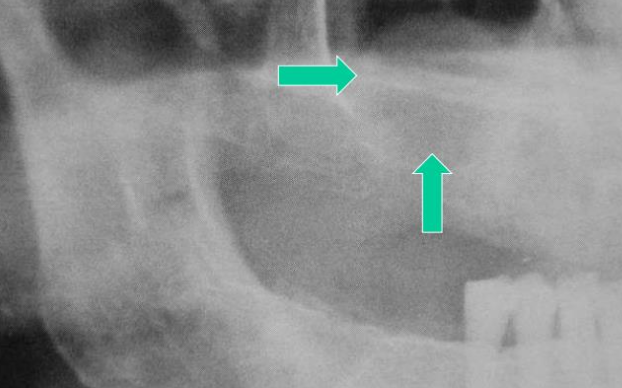

Sialolithiasis (唾液腺結石症) 和鈣、磷的代謝無關 Submandibular gland -

• 單發

• 用餐 30mins 痛

• 硬、不移動

• 檢測需要 occlusal film